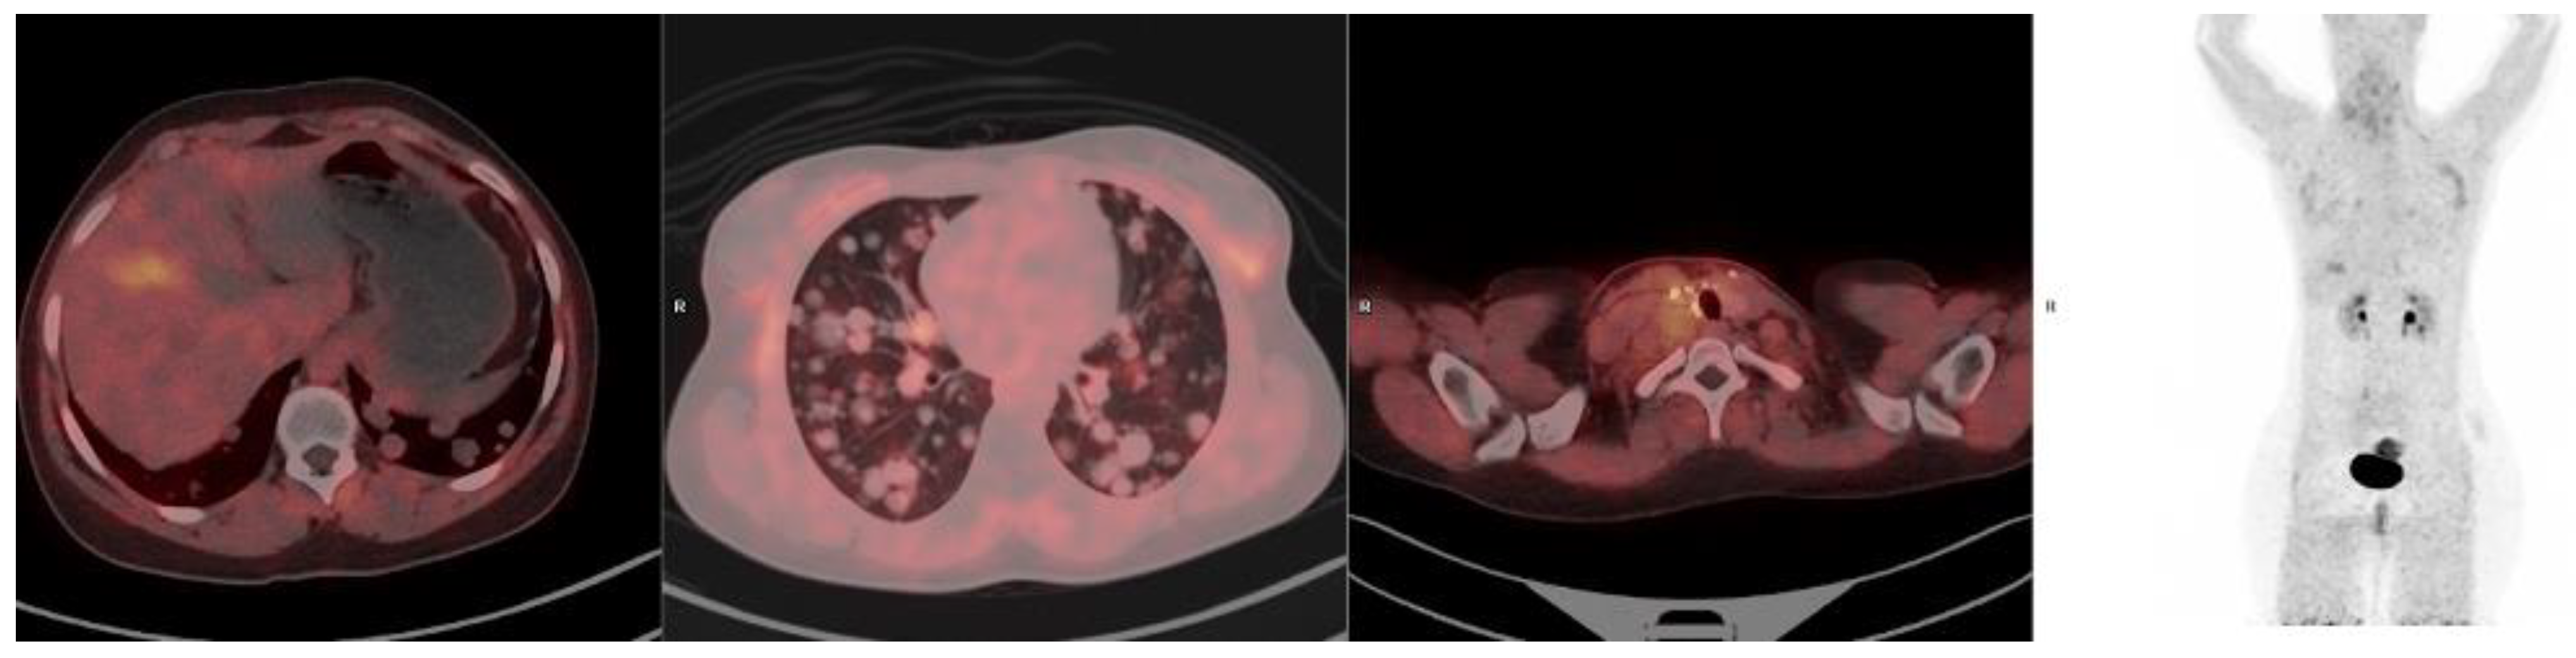

FAPI-Based Radioligands

3.10. Pancreatic Cancer

3.11. Hepatocellular Carcinoma